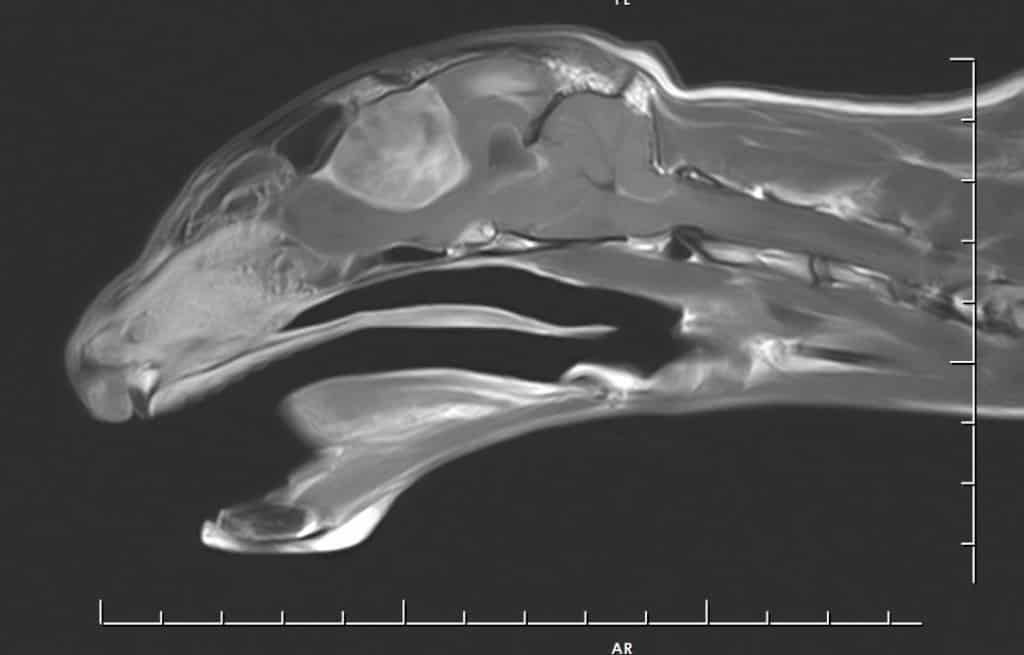

Specialist vets at a leading UK animal hospital discovered that a giant brain tumour was the cause of a cat’s episodes of collapses and general unsteadiness.